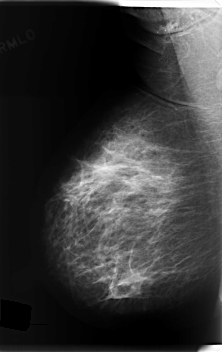

C_0203_1.LEFT_MLO

LEFT_MLO LINES 6016 PIXELS_PER_LINE 3144 BITS_PER_PIXEL 12 RESOLUTION 50 OVERLAY